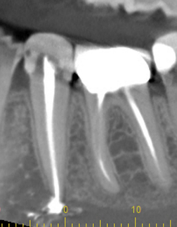

Canals cleaned and shaped to the apex?

The filling should go to the tip of your root. Not filling enough (under-fill) can leave space for harmful bacteria to grow. A filling that goes beyond the root tip (over-fill) can cause damage to the bone, sinus, or even nerve damage in severe cases. Over or under filling increases the chances that you'll need to have another procedure down the road.

Adequate root filling density?

The canals should be filled without leaving any spaces between the walls of the tooth. Spaces can leave room for bacteria and toxins that eventually cause an infection, often requiring another root canal.